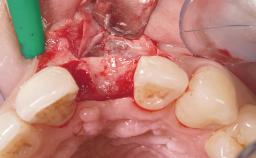

A 42-year-old female patient was referred to our clinic at the School of Dentistry of the University of São Paulo in November 2004, presenting a deficient restoration in the upper left central incisor. The clinical examination revealed no gingival retraction or any signs of gingival inflammation and, therefore, previous periodontal treatment was not considered. The patient presented a high lip line at full smile and a thin tissue biotype. This combination characterized a high-risk situation from an anatomic point of view, which required careful preoperative planning and cautious surgical execution.

Soft Tissue Grafting None

Soft Tissue Anatomy Intact Defective

Soft Tissue Contour and Volume Ideal